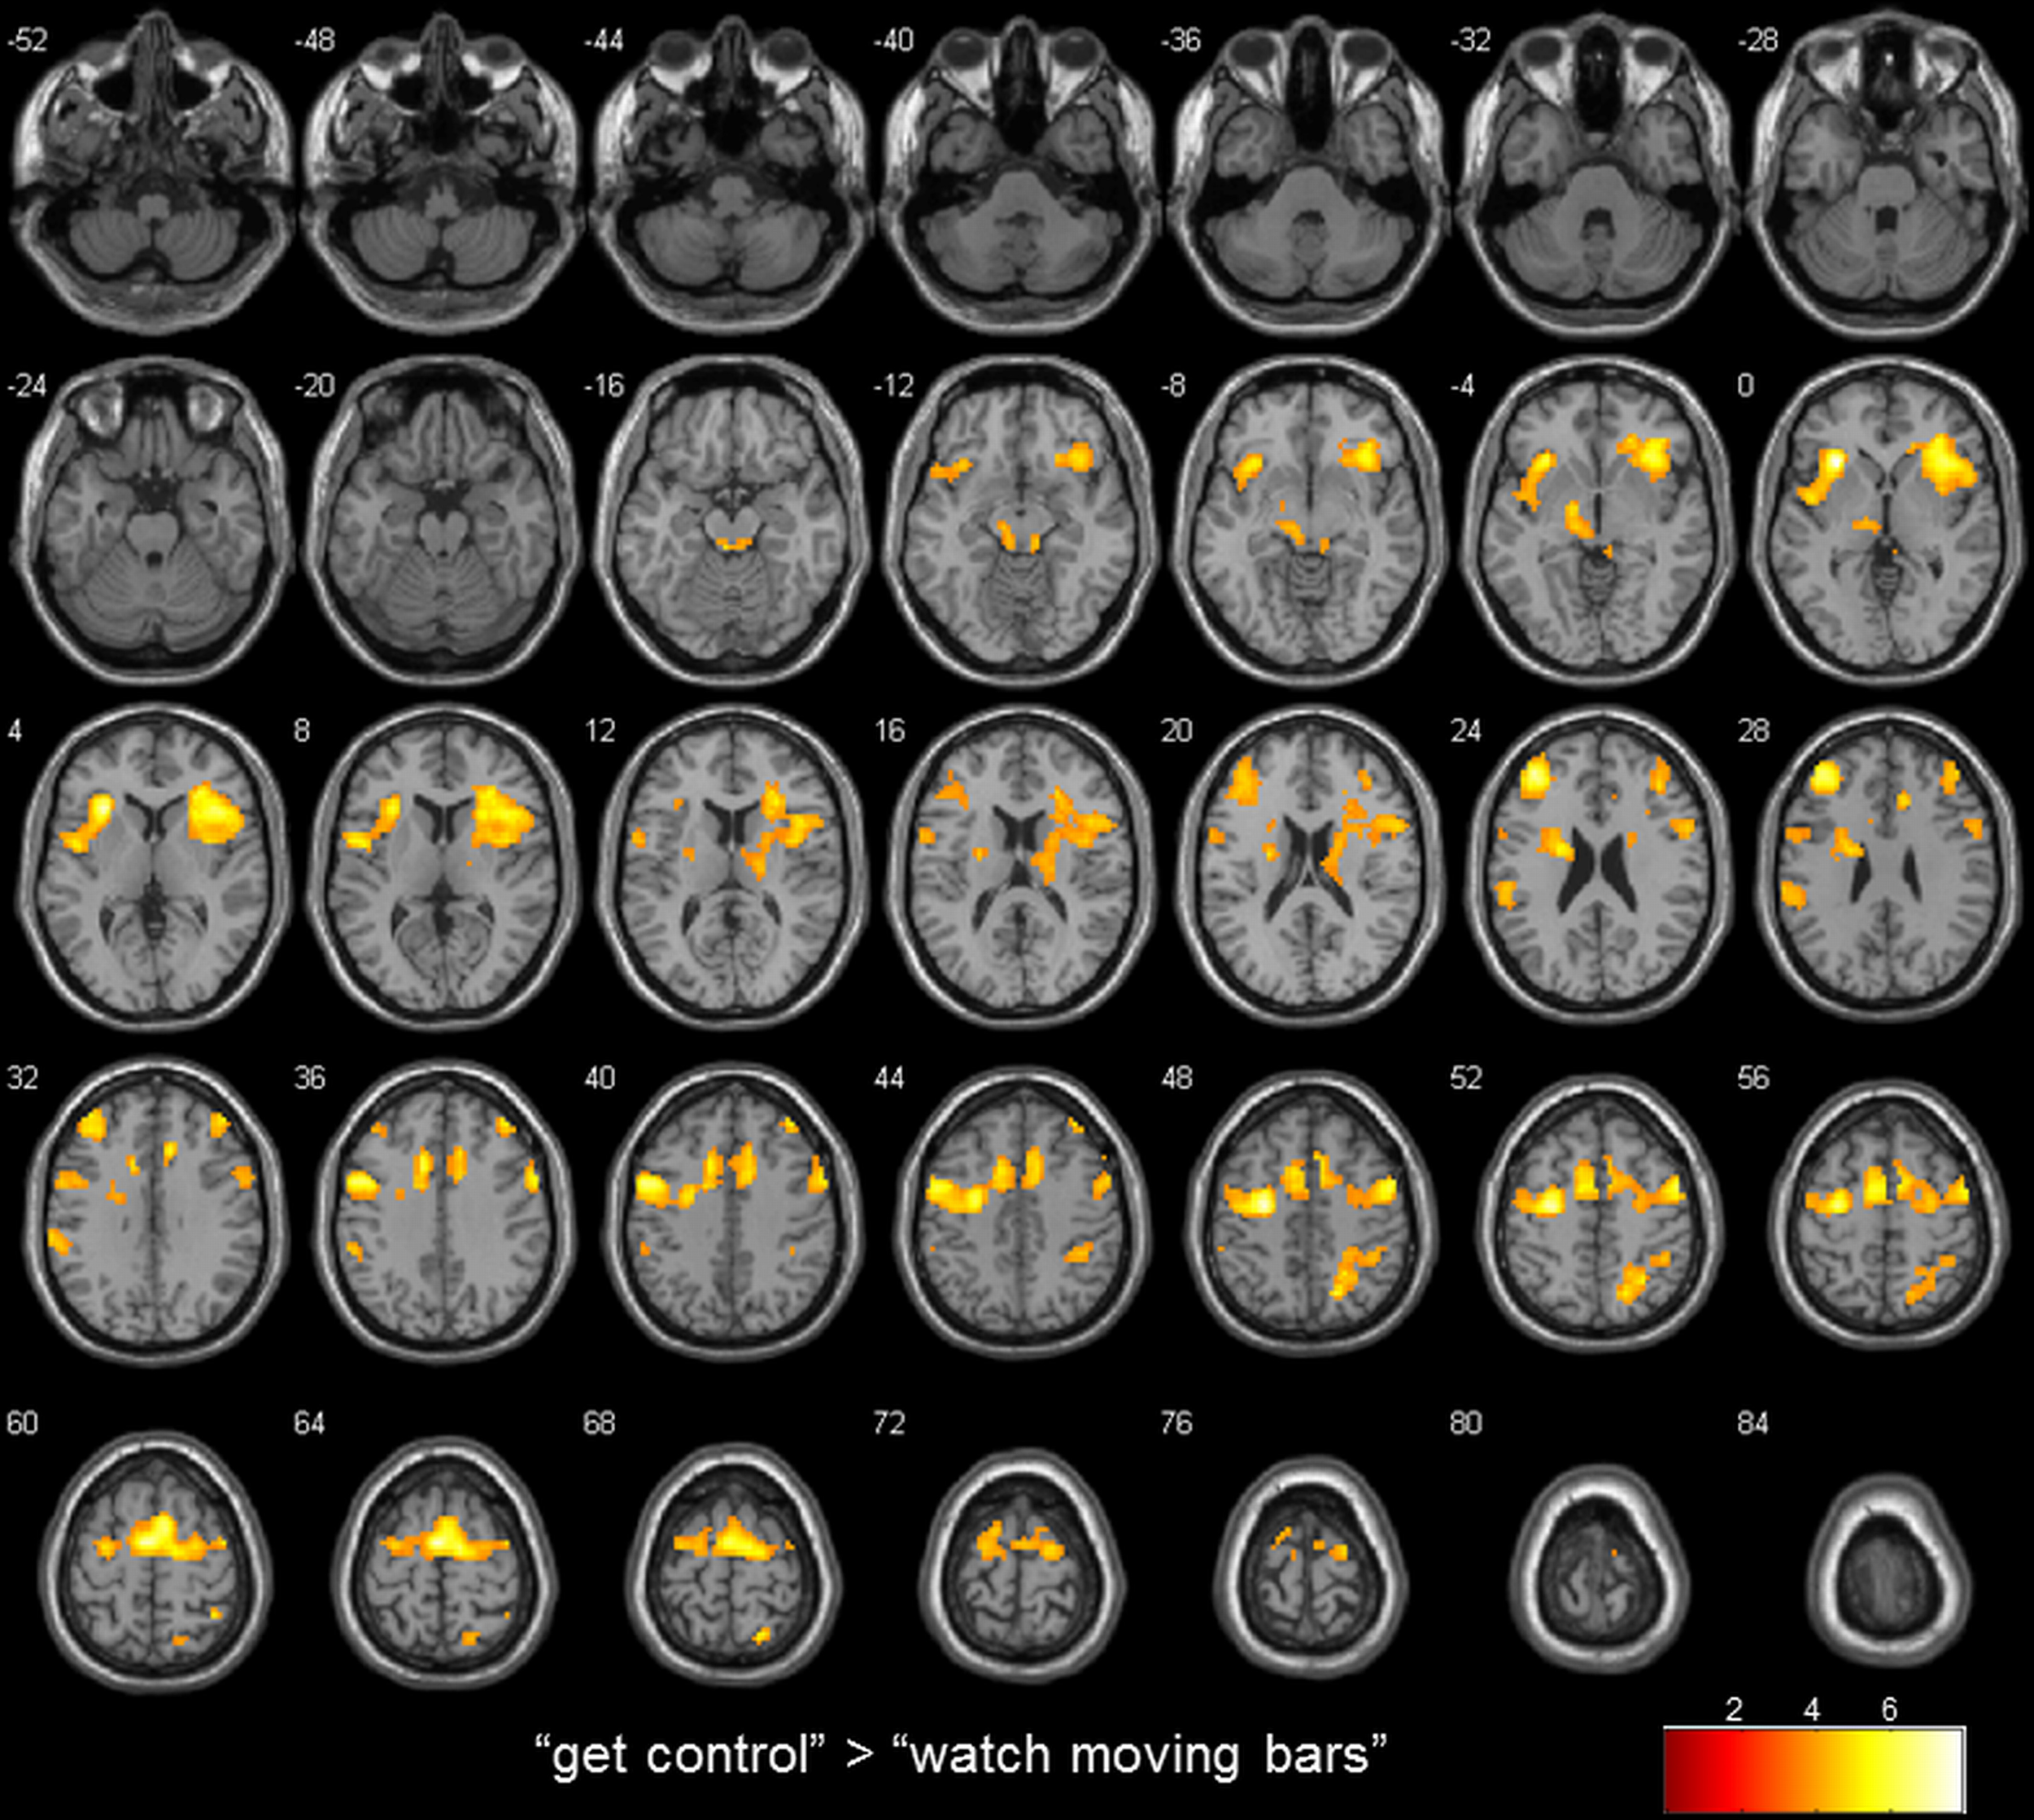

Whole brain analysis results are reported at a threshold of p < 0.001 uncorrected in pictures and p < 0.05 corrected for multiple comparisons on cluster-level [false discovery rate (FDR)] with a minimum cluster size of 10 voxels in tables. All reported coordinates are reported in MNI space (Table 2; Figure 2).

FIGURE 2

www.frontiersin.org

Figure 2. transversal slices (4 mm spacing); t-score map for “get control” “watch moving bars”; p < 0.001 uncorrected on voxel-level, p < 0.05 corrected for multiple comparisons on cluster-level [false discovery rate (FDR)]; minimum cluster size 10 voxels.

To examine the extent to which self-referential processes are relevant for the perceived level of control over a NF-like task, we contrasted the conditions “get control” and “watch moving bars.” Importantly, this contrast revealed several highly significant activation clusters. A widespread activation has been identified in frontal areas with its peak in the left anterior part of the insula. Additionally, a large cluster of activation including the right insula dorsomedial and lateral prefrontal and bilateral supplementary motor area as well as the anterior part of the cingulate gyrus. Furthermore, this comparison also revealed significant cluster activation in the right superior parietal lobe, right middle frontal gyrus, left supramarginal gyrus and left thalamus. The corresponding Brodmann areas of these significant activation clusters are listed in Table 2. In contrast during the simply watching trials, compared to attempt of controlling the bars, significant activation has been identified only in left angular gyrus (Table 2; Figure 2).